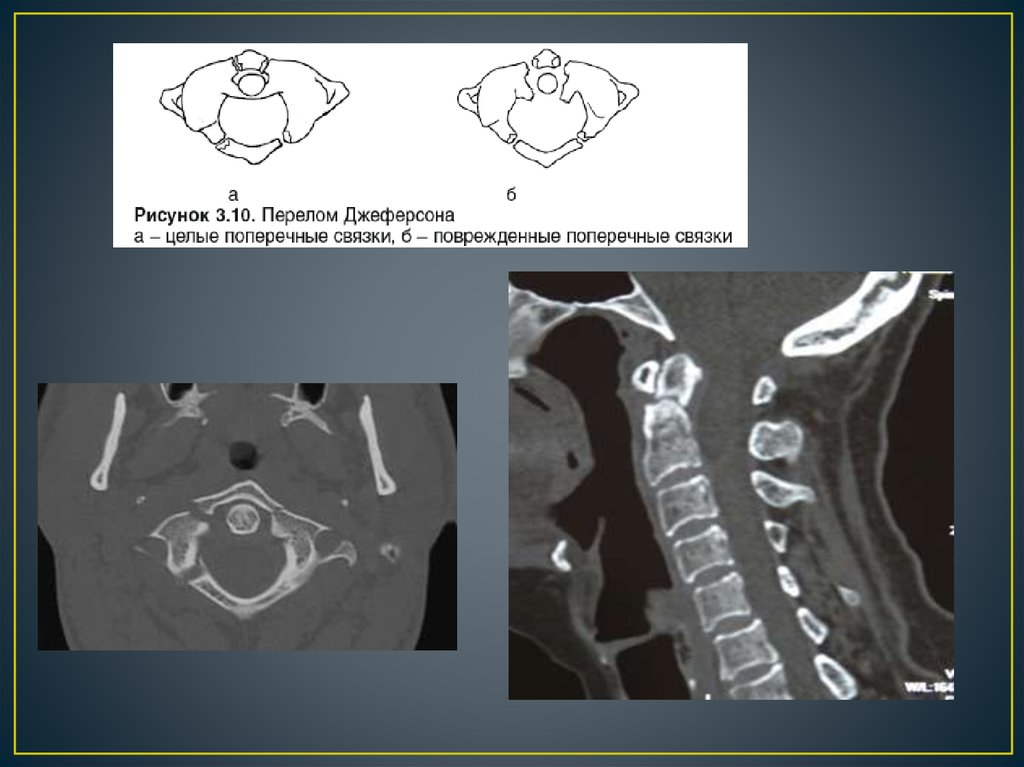

Позвоночно – спинальная травма